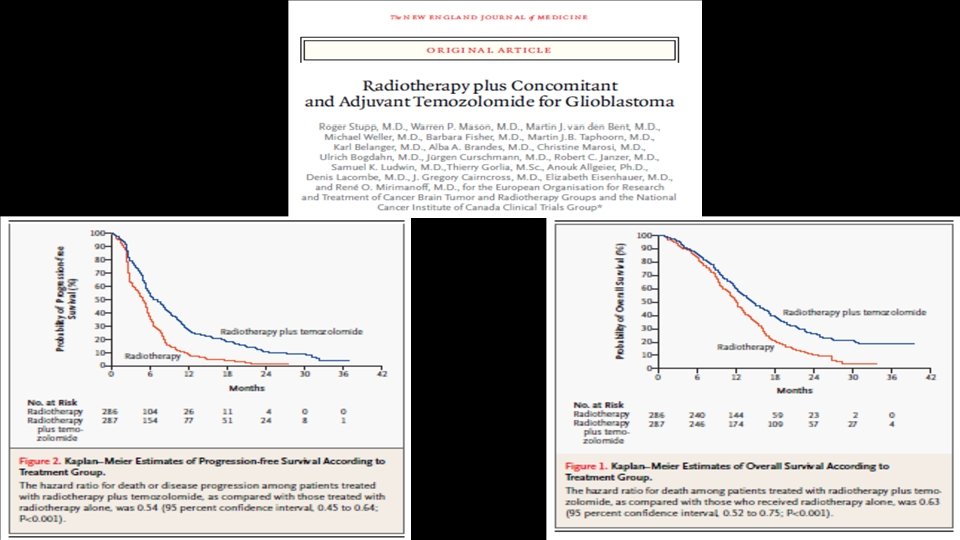

Glioblastoma Treatment • Gross Total Resection of Contrast-Enhancing area , if possible Stupp Regimen (External Limited Field Radiation and Concurrent Temozolomide followed by TMZ alone) • Gliadel, Avastin, Optune (TT Fields)- FDA approved

Limited external field radiation (tumor cavity and 2 cm around it) + Temozolomide x 6 weeks Followed by Temozolomide for 6 months+